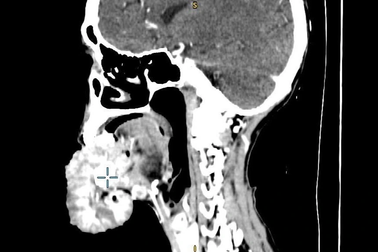

Bác sĩ choáng váng với khối u phủ kín miệng người bệnhKhi khám cho bệnh nhân, bác sĩ choáng váng bởi khối u vùng miệng có kích thước khủng (lên đến 20cm). Khi mới nhú khối u cách đây 3 năm, bệnh nhân không đi khám mà áp dụng ăn thực dưỡng.